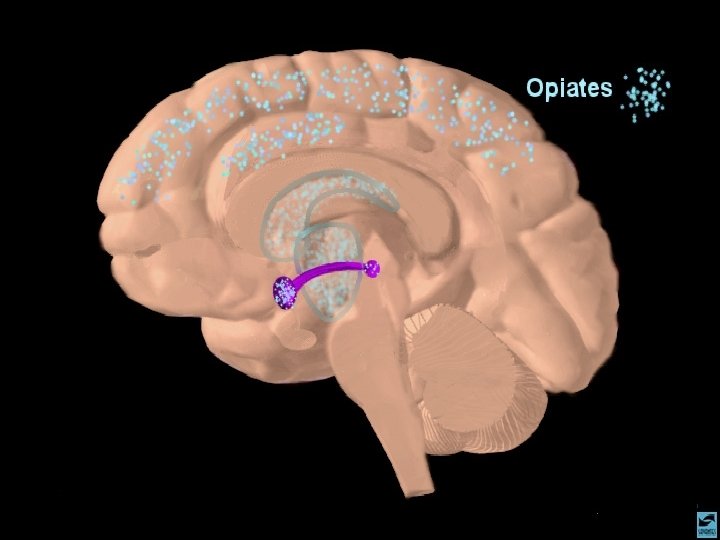

OS OPIÁCIOS INFORMAÇÕES GERAIS 1 - PODEM SER NATURAIS OU SINTÉTICOS 2 - SÃO UTILIZADOS NA MEDICINA COMO ANALGÉSICOS POTENTES 3 - CAUSAM INTENSA DEPENDÊNCIA FÍSICA 2 - MUITAS DEPENDÊNCIAS INSTALAM-SE NO USO CLÍNICO 5 - RAPIDAMENTE ESTABELECEM TOLER NCIA 4 - A HEROÍNA É UMA DROGA ILEGAL QUE ESTÁ RAPIDAMENTE DIFUNDINDO-SE

OS OPIÁCIOS EFEITOS CEREBRAIS OS OPIÁCIOS LIGAM-SE AOS RECEPTORES CEREBRAIS DE ENDORFINAS